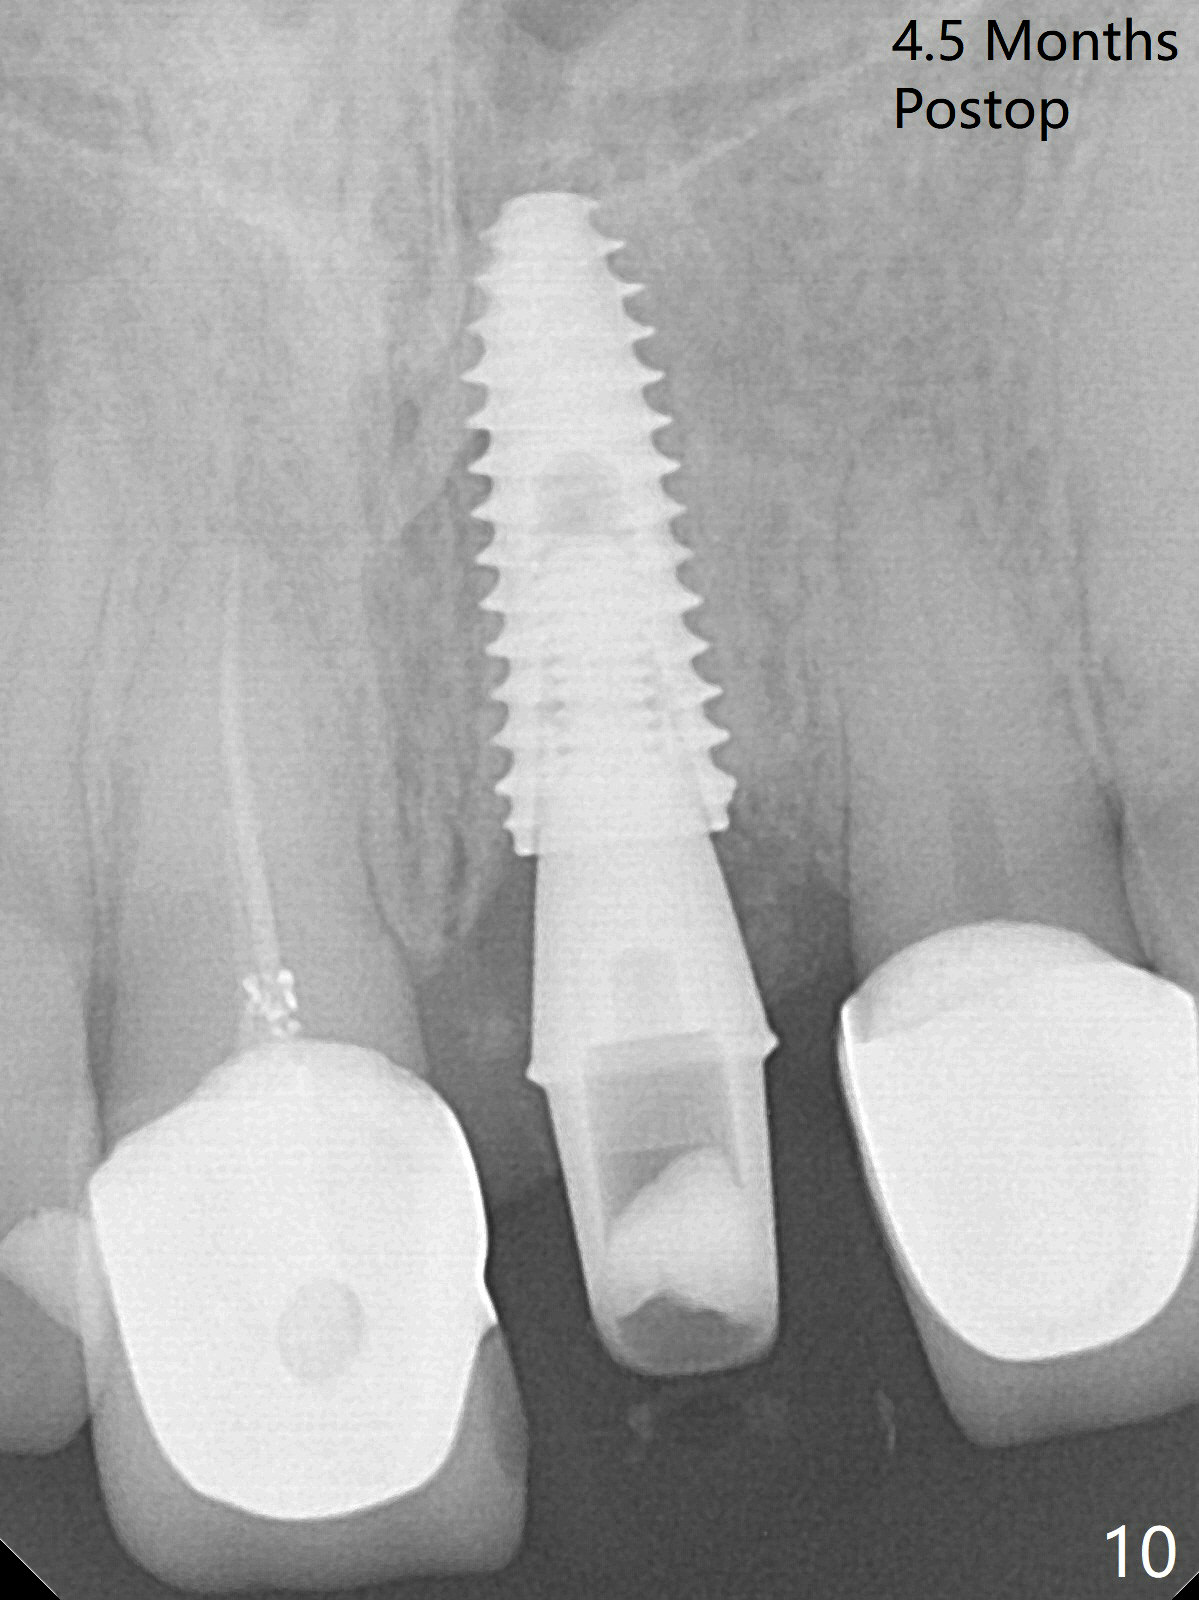

After sectioning the splinted crowns at #8 and 9 (Fig.1,2 (*: open bite)), the tooth #9 is deemed nonsalvageable because of caries and the crown/retainer of #8 is recemented. The trajectory of initial osteotomy is off (Fig.3 (red line: ideal trajectory)). Using Lindamann bur twice does not improve the trajectory (Fig.4,5). It appears that a new osteotomy should be established in the distal wall of the socket (Fig.5 red line (initial entry point and angle), Fig.6). Following sequential osteotomy, a 4x10 mm dummy implant is placed with stability and ~ 3.5 mm apical space (Fig.7 red line). A final implant (4x11.5 mm) is placed subcrestal (except buccal, Fig.8). With further placement of the implant, a 4.5x5.5(3) mm abutment and Vera graft are placed (Fig.9) prior to fabrication of an immediate provisional. In all, a new osteotomy site should be set up when the trajectory is to be changed substantially. There is no gross bone loss 4.5 months postop (Fig.10). There is shade mismatch when a porcelain-fused-Zirconia crown is tried in (Fig.11, as compared to Fig.1). The latter is corrected when a PFM crown is cemented (Fig.12).